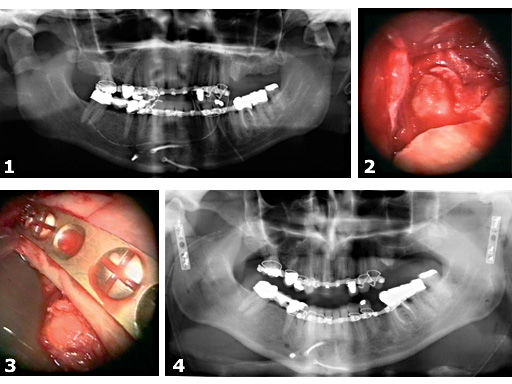

Fig 1

Panoramic radiograph preoperatively of a severely dislocated bilateral condyle fracture. Lag screw fixation of the median mandibular fracture was performed prior to admission in another clinic. Note the severely dislocated fragments with medial override on the right and medial displacement with shortening of the ascending ramus on the left side.

Fig 2

Intraoperative view by a 30 degree angled endoscope of the dislocated condyle fracture on the right side. The condylar fragment was dislocated with medial override.

Fig 3

The condylar fragment was reduced by the special instruments of the Subcondylar / Ramus Fixation System. Endoscopic view after osteosynthesis with a 2.0mm titanium miniplate. The alignment of the fragments was controlled endoscopically at the posterior aspect of the ascending ramus.

Fig 4

Panoramic radiograph postoperatively after endoscopic assisted reduction and fixation of both condylar fractures.